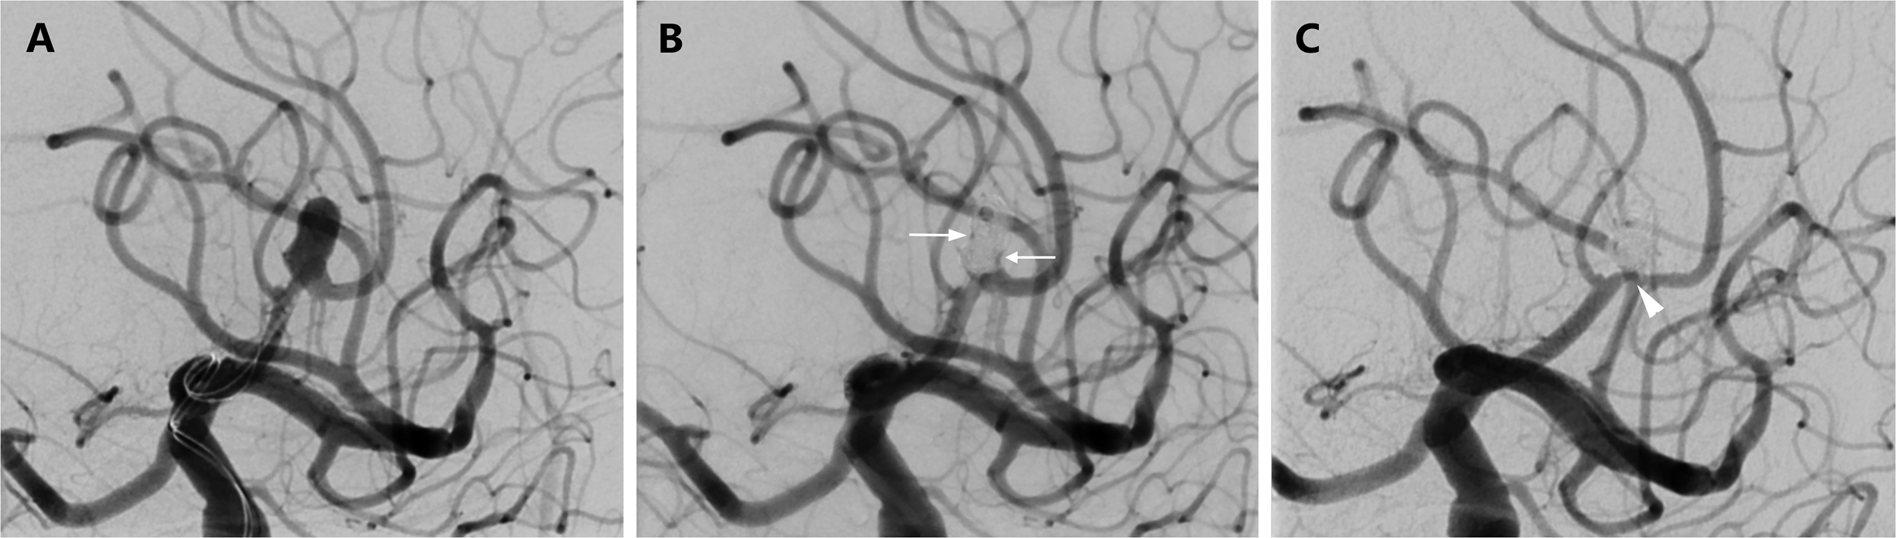

Figure 2

Initial treatment result and follow-up after SAC of an aneurysm at the pericallosal artery with the jailing technique. (A) Working projection with microcatheters immediately proximal to the aneurysm. The aneurysm develops from the apex of a sharp curve. A little further distally again sharp bend of the vessel. (B) Result immediately after the intervention. Still little inflow into the aneurysm sac (RROG 3, white arrows). Note the slightly different vascular anatomy after stenting. (C) In the control-DSA after 6 months complete aneurysm occlusion (RROG 1). Note the discreet intimal hyperplasia in the region of the aneurysm ostium (white arrowhead).